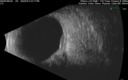

61 year old man with amelanotic choroidal nevus. Vision Normal - Stable over 4 years.

Amelanotic Choroidal Nevus - Multimodal Imaging577 views61 year old man with amelanotic choroidal nevus. Vision Normal - Stable over 4 years.00000